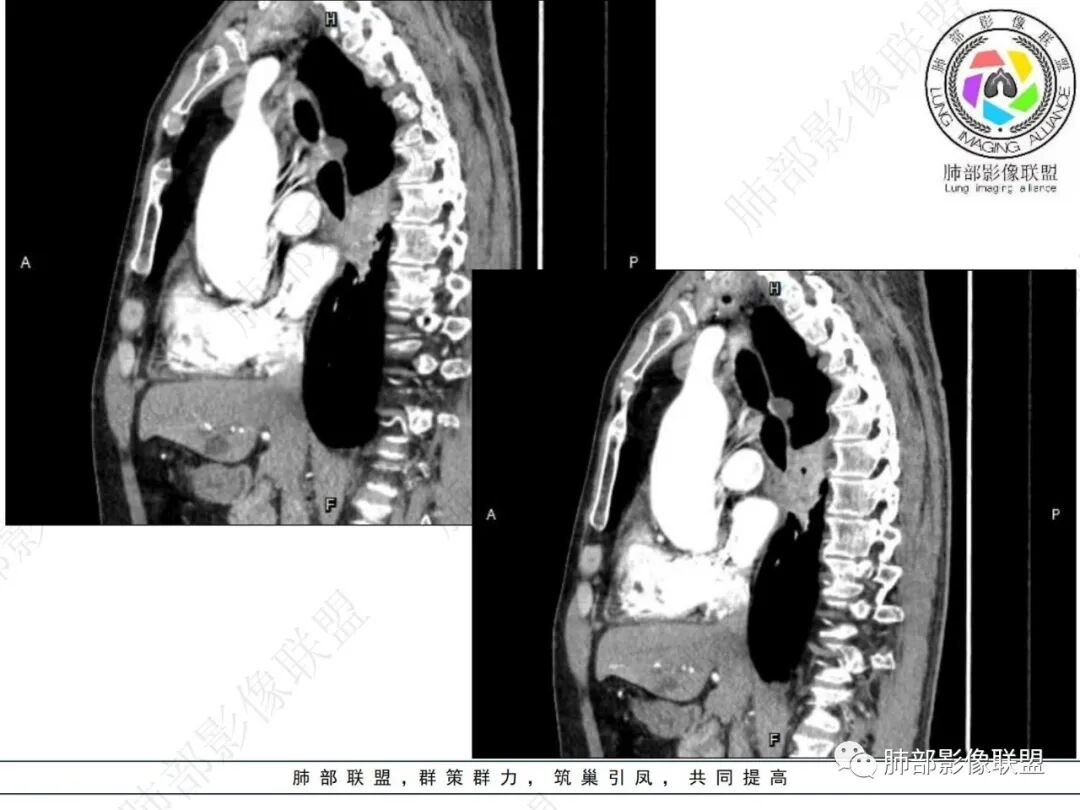

气管隆突下团片影,其内积气,与食道分界不清,食道壁增厚,管腔狭窄,右下肺实变影,支气管壁增厚,考虑食管支气管瘘并右下肺感染,食道肿瘤病变不除外

支持食管支气管瘘(考虑食管癌)伴后纵隔及右肺感染,食管管壁明显增厚,管腔狭窄,相邻右侧后纵隔内软组织内可见气体影,与食管分界不清,右肺有实变及不张。

右肺下叶背段条片状实变影,内可见支气管走行,支气管有狭窄有扩张,周围可见磨玻璃影,隆突下团片影,内密度不均可见气体影,与周围结构界限不清。食管下段壁增厚,管腔狭窄,右肺下叶慢性炎、肺不张,考虑食道肿瘤所致气管食管瘘。

右肺下叶沿肺叶肺段分布斑片、条片状影,以下叶背段为显,边缘模糊,内可见支气管走行,局部支气管管壁增厚,右侧胸腔少量积液。纵隔隆突下可见不均匀软组织密度影,与周围结构分界不清,内见气体密度影,与食管及相邻右肺支气管之间未显示通道。邻近食管下段壁明显不规则增厚,增强后食管管壁明显不均匀强化,可见线样强化的连续完整粘膜影。

3.综合分析:

右肺下叶片影,气道相关,符合感染性病变。纵隔隆突下软组织密度影,异常气体影,长病程,起病缓慢,提示存在气管或食管瘘。食管镜未见明显新生物形成,临床未提供进食或饮水呛咳临床表现,综合分析应该考虑支气管瘘的形成。

对比患者3月份的CT图,原隆突下存在增大钙化淋巴结,现在出现气体影,且钙化显示不清,应想到淋巴结结核破溃成瘘可能性。